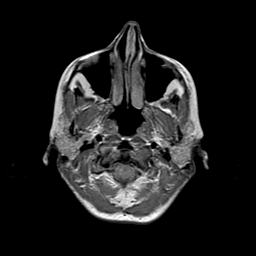

Metastatic bronchogenic carcinoma: proton density-weighted MR -- Slice #0

[Home][Help][Clinical] Slice 0